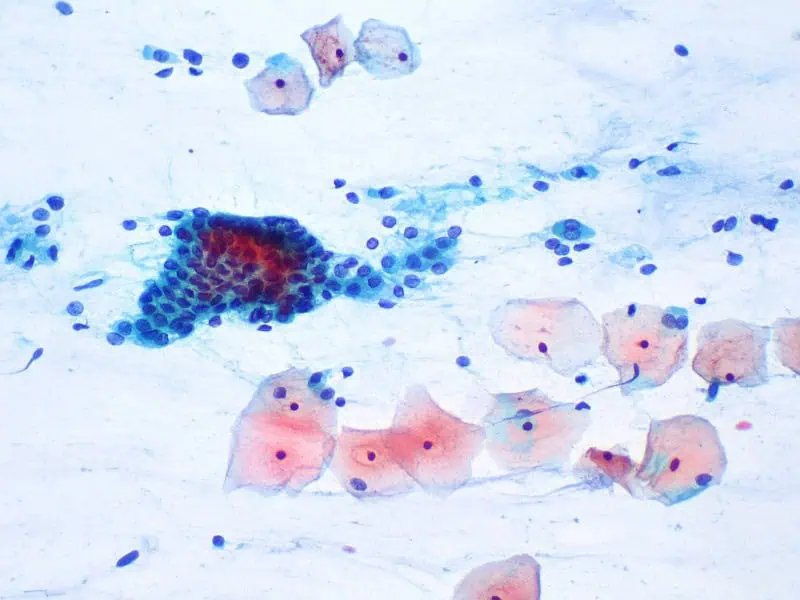

Odebrané buňky jsou natřeny na sklo a zafixovány alkoholovým roztokem. Nedílnou součástí stěru je i dobře vyplněná průvodka k vyšetření, obsahující informace o datu posledního menstruačního krvácení, užívání antikoncepce či délce trvání těhotenství. Fixovaný preparát cytologického stěru je s dokumentací odeslán k vyhodnocení do cytologické laboratoře, kde odborník-cytolog vyšetří a nález se podrobně popíše. K hodnocení je aktuálně v České republice využívána cytologická klasifikace přijatá v USA ve městě Bethesda v roce 2001.

Po velmi podrobném a jednoznačném popisu následuje doporučení dalšího postupu. Cytolog zhodnotí kvalitu stěru, hormonální stav ženy a případnou infekci a zařadí pozorované buňky děložního hrdla do příslušné kategorie.

Zjednodušeně je možné popsat 3 různé skupiny výsledků: 1. nálezy normální, 2. nálezy nejasné a 3. nálezy abnormální. V případě nejasných nebo abnormálních výsledků je doporučena kontrola cytologického stěru v kratším intervalu, obvykle za 3–6 měsíců, případně kolposkopické vyšetření ve specializované ambulanci Centra onkologické prevence (běžně používaná zkratka COP).